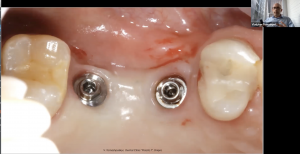

Операционный микроскоп является штатным оборудованием любого стоматологического кабинета. Работа с микроскопом позволяет хирургу стоматологу избавить своих пациентов от необоснованных страданий, а так же работать эргономично, что сохраняет здоровье доктора на долгие годы. Информация, полученная на данном вебинаре, позволит Вам лучше разобраться с необходимыми характеристиками микроскопа и знать основные понятия при работе с таким оптическим устройством. Материал вебинара предоставляет фактические рекомендации по работе хирурга-стоматолога с различным уровнем навыка, от старта до микрохимрургических манипуляций. Дан обзор некоторых возможных, при работе с операционным микроскопом, мало-инвызивных методов аугментации кости и манипуляций мягкими тканями.